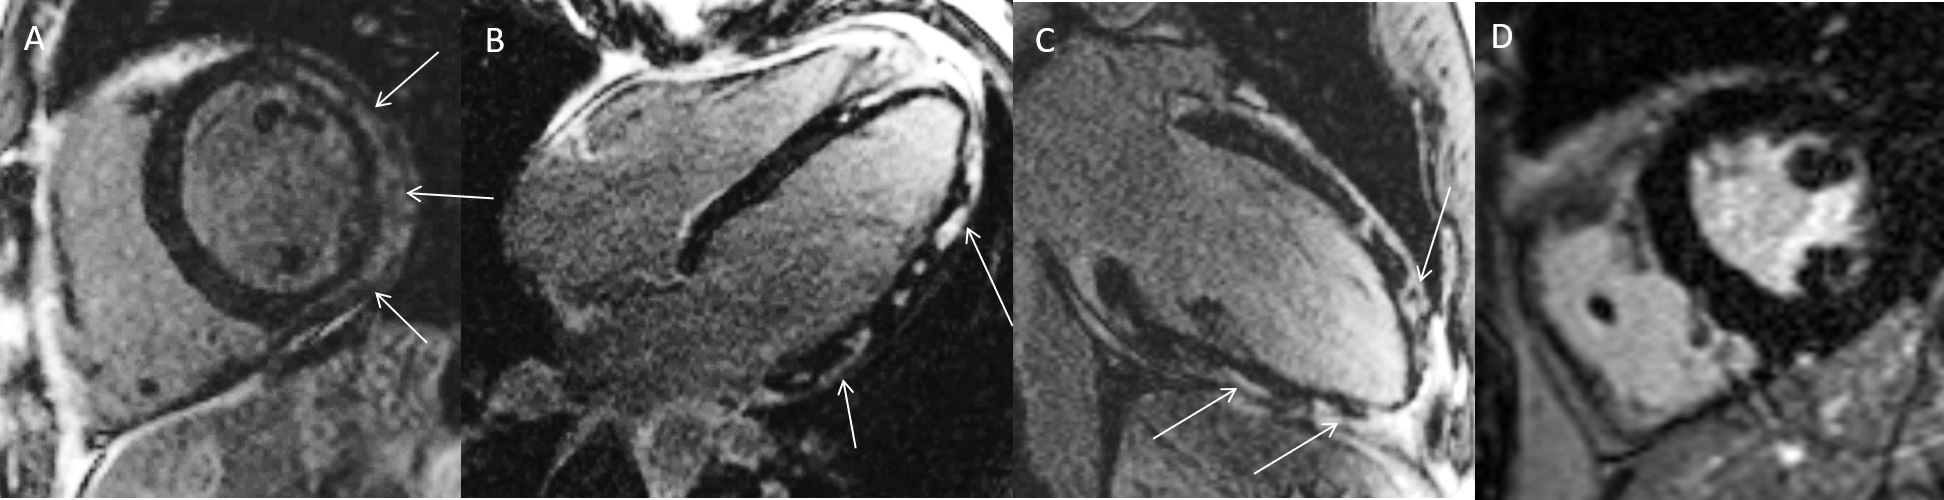

MRT Aufnahme mit Mapping Verfahren

44-jährige Patientin mit stattgehabtem Infekt der oberen Atemwege und Brustschmerzen. Bei erhöhten Herzenzymen Durchführung einer Herzkatheteruntersuchung, welche keine Engstellen zeigen konnte. Im CMR kein Nachweis eines LGE (A), allerdings erhöhtes natives T1 (1180ms, Norm: <990ms) [B] sowie erhöhtes T2 (64ms, Norm: <50ms) [C] als Hinweis auf Myokarditis ohne fokale Narbenbildung. Die neueren Mapping-Verfahren erlauben den Nachweis einer diffusen Herzschädigung, wobei erhöhte T1-Werte vor allem narbige Veränderungen, und erhöhte T2-Werte akut-entzündliche Prozesse anzeigen können. Beide Prozesse können im Rahmen einer Myokarditis auftreten.